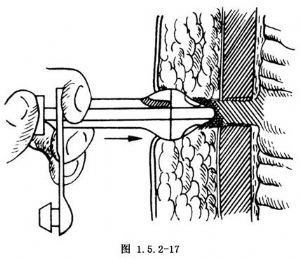

操作时,患者口咽部喷雾局部麻醉,仰卧于手术台上,头侧略抬高,将纤维胃镜经口插入胃腔。上腹部常规消毒,铺消毒巾。内镜医师通过胃镜向胃内充气使胃扩张、结肠下移、胃前壁紧靠前腹壁,直视下将胃镜端抵住胃前壁,同时将房间灯光转暗,观察上腹部由胃镜透照出的光亮区。这一部位通常是在肋缘与脐之间的中点(图1.5.2-12),消瘦病人从该处可以触到胃镜端。在透光处做一个标记,将胃镜退回少许,检查一下选点是否合适。于标记处做局部麻醉,切开皮肤长1cm,用16号斜面导管针经切口穿刺,通过腹壁及胃壁进入胃腔。同时内镜医师应观察到穿入胃腔的针头。这些步骤应迅速完成,以减少胃从腹壁向后移的机会。拔除穿刺针芯从外套管内插入一粗的不吸收线或尼龙缝线。内镜医师通过胃镜插入一息肉圈套器将不吸收线套住,然后拉住不吸收线连同胃镜一起从病人口腔内退出(图1.5.2-13)。将带有内衬垫的de Pezzer导管(图1.5.2-14)或PEG专用导管牢牢固定在口腔侧长线上。导管端必须呈锥形,必要时可做一锥状塑料套管套住de Pezzer导管的开口端。长线及导管端涂上无菌水溶性润滑剂将腹侧端长线轻柔、稳定持续地向外牵拉使锥形导管被牵拉拖入食管进入胃腔并由腹壁穿刺孔拖出(图1.5.2-15)。再次插入胃镜确认置入的导管位置是否正确并及时加以调整。腹壁外放置外衬垫或圈状物,将导管与衬垫固定在皮肤上,注意松紧要适度,不宜过紧,以防皮肤压迫坏死(图1.5.2-16)。4周后,胃前壁已与腹壁牢固附着,可以改用硅胶代用品导管并可以装配一合适的堵塞器装置(图1.5.2-17,1.5.2-18)。